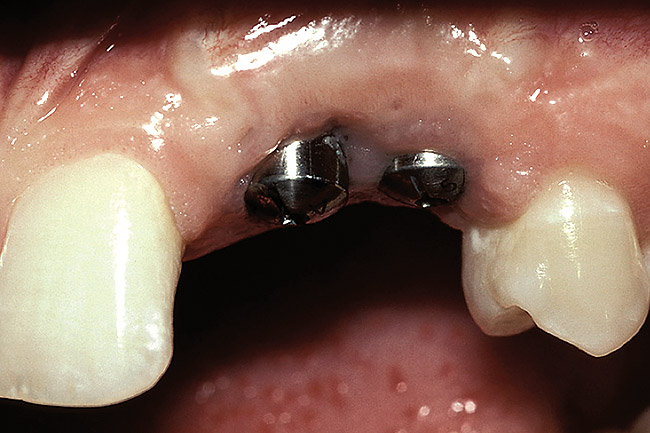

Figure 4  If the interproximal crest of bone is between adjacent implants, the average papilla height above the bone is 3.5 mm (ie, red line), which results in a significant difference in papilla height when compared to the pre-extraction papillary height (ie, yellow line).

Figure 4